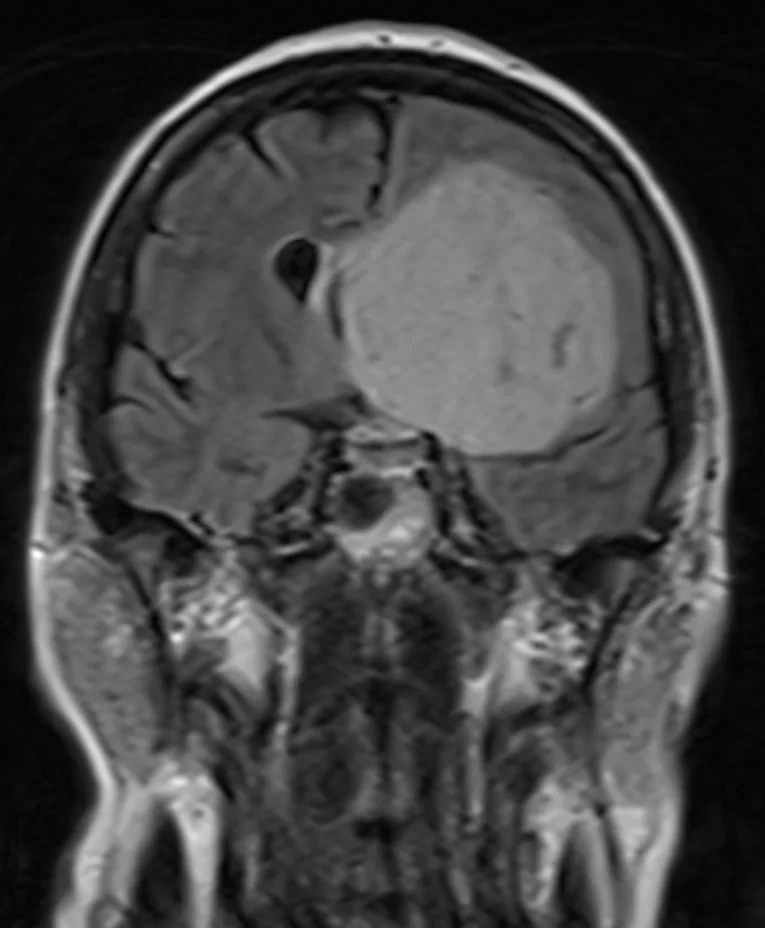

Χωροκατακτητική Εξεργασία δεξιού Κροταφικού Λοβού

Ασθενής άνδρας, 31 ετών με επεισόδια κεφαλαλγίας. H Μαγνητική Τομογραφία εγκεφάλου ανέδειξε εκτεταμένη χωροκατακτητική εξεργασία δεξιά κροταφικά με πίεση επί του σύστοιχου κροταφικού κέρατος και

Περισσότερα